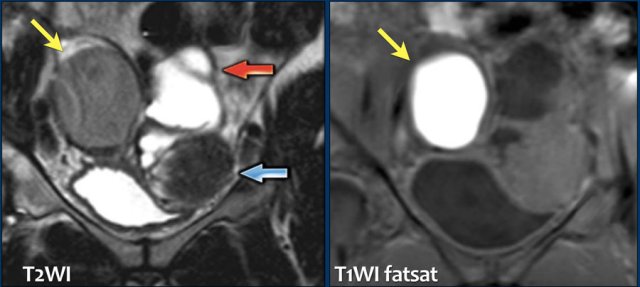

The T2-images show endometriosis infiltrating the bladder wall.

The sagittal T2-image shows full-thickness bladder endometriosis with isointense signal compared to muscle and foci of high signal intensity, indicating dilated endometrial glands.

The fatsat T1-image shows small cysts with hyperintense signal within the lesion caused by hemorrhage.